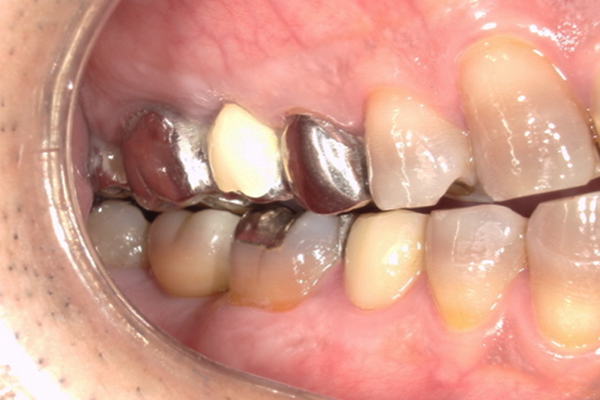

| 主訴 | 歯が痛い |

|---|---|

| 治療内容 | 右上奥歯に対するインプラント治療 (今後右下に対してもインプラント治療を予定) |

| 治療期間 | 6ヶ月 |

| 治療費 | 44万5千円 |

| 治療 リスク | インプラントを埋入したあと3ヶ月程度待ち時間が必要。 その期間は仮歯を使用していただきます。 |